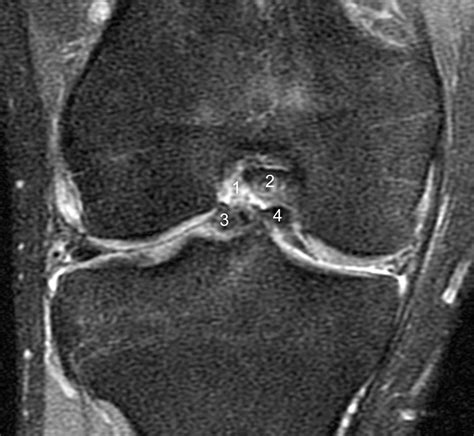

| MRI Scan | Provides elaborated images of soft tissue to confirm the tear location and pattern. |

⚠️ Tone: While an X-ray is utile, it can not visualize the meniscus. An MRI is the golden standard for diagnose a pail handle tear because it reveal the specific constellation of the displaced cartilage.

In succinct, while a meniscus bucketful handle rent is a serious trauma that ofttimes demand operative intervention, mod orthopedic techniques offer excellent outcomes for those who assay timely treatment. By focusing on accurate diagnosis through MRI imaging, select repair when potential to preserve the shock-absorbing function of the stifle, and rigorously adhere to a structure post-operative renewal programme, most individuals can successfully restore their genu's use. Always refer with an orthopedic specialist as presently as you notice signs of mechanical locking or unrelenting swelling, as nimble action is the key to protect your long-term joint health and maintain an active, pain-free lifestyle.

- meniscus bucket handle tear mri